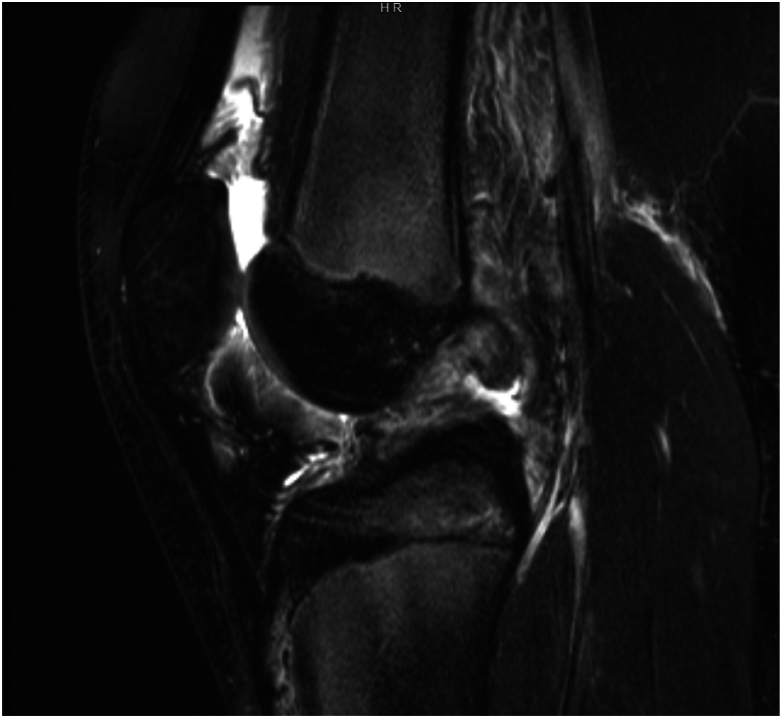

Lateral extra-articular tenodesis (LET), as an adjunct to anterior cruciate ligament (ACL) reconstruction, is gaining popularity among pediatric and sports medicine orthopaedic surgeons for the treatment of ACL injury, especially in the female, hyperflexible, and high-risk athlete population. The addition of LET or anterolateral ligament (ALL) reconstruction is typically recommended at the time of index ACL reconstruction surgery and is performed after the ACL graft is tensioned. Rotational instability has been described in cases where the ACL graft was malpositioned too vertically, and in those cases, ACL revision is indicated. In our case, ACL reconstruction was performed in isolation in a hyperflexible, high-risk (volleyball) female athlete, and she had persistent complaints of rotational instability despite an intact and well-positioned ACL graft on magnetic resonance imaging (MRI) scan. She demonstrated excessive internal rotation of the tibia in relation to the femur and exhibited symptomatic anterolateral instability on clinical examination, with a negative pivot shift but pain on internal rotation stress. She underwent a second surgery consisting of isolated modified Lemaire LET after examination under anesthesia (EUA) demonstrated negative Lachman and pivot shift. Second-look arthroscopy demonstrated an intact quadriceps autograft ACL graft. She recovered uneventfully, and her rotational instability problem was resolved. She returned to sports 12 months after the surgery and has been pleased with her result.

Key concepts: (1)Lateral extra-articular tenodesis (LET) can be added to increased rotational stability in the setting of anterior cruciate ligament (ACL) reconstruction.(2)Although typically added during the index procedure, it can be successfully completed later if needed.(3)The ACL confers both anteroposterior and rotational stability to prevent excessive anterior translation and excessive internal rotation of the tibia with respect to the femur.(4)LET can augment the ACL graft in preventing rotational instability in the setting of an ACL-deficient knee.